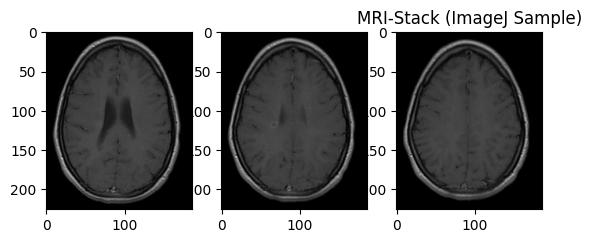

オープンデータで試す(脳MRI画像)

医療系の画像の場合、一枚では済まないことが多い。

上記の例では画像は1枚のみの入力となっている。

ここでは、脳MRI画像3枚を使って、推論結果を得られるようほんの少しだけ工夫した。

# この画像で試しました。

# ソース:https://imagej.net/ij/images/mri-stack.zip

image_paths = [

"/home/tatsunidas/AI aided Image Interpretation/mri-stack18.jpg",

"/home/tatsunidas/AI aided Image Interpretation/mri-stack19.jpg",

"/home/tatsunidas/AI aided Image Interpretation/mri-stack20.jpg"

]